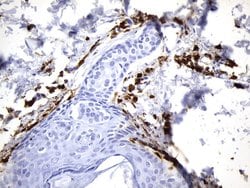

F13A1 Mouse anti-Human, Clone: UMAB243, liquid, UltraMAB™

This gene encodes the coagulation factor XIII A subunit. Coagulation factor XIII is the last zymogen to become activated in the blood coagulation cascade. Plasma factor XIII is a heterotetramer composed of 2 A subunits and 2 B subunits. The A subunits have catalytic function, and the B subunits do not have enzymatic activity and may serve as plasma carrier molecules. Platelet factor XIII is comprised only of 2 A subunits, which are identical to those of plasma origin. Upon cleavage of the activation peptide by thrombin and in the presence of calcium ion, the plasma factor XIII dissociates its B subunits and yields the same active enzyme, factor XIIIa, as platelet factor XIII. This enzyme acts as a transglutaminase to catalyze the formation of gamma-glutamyl-epsilon-lysine crosslinking between fibrin molecules, thus stabilizing the fibrin clot. It also crosslinks alpha-2-plasmin inhibitor, or fibronectin, to the alpha chains of fibrin. Factor XIII deficiency is classified into two categories: type I deficiency, characterized by the lack of both the A and B subunits; and type II deficiency, characterized by the lack of the A subunit alone. These defects can result in a lifelong bleeding tendency, defective wound healing, and habitual abortion.Specifications

| Immunohistochemistry (Paraffin) | |